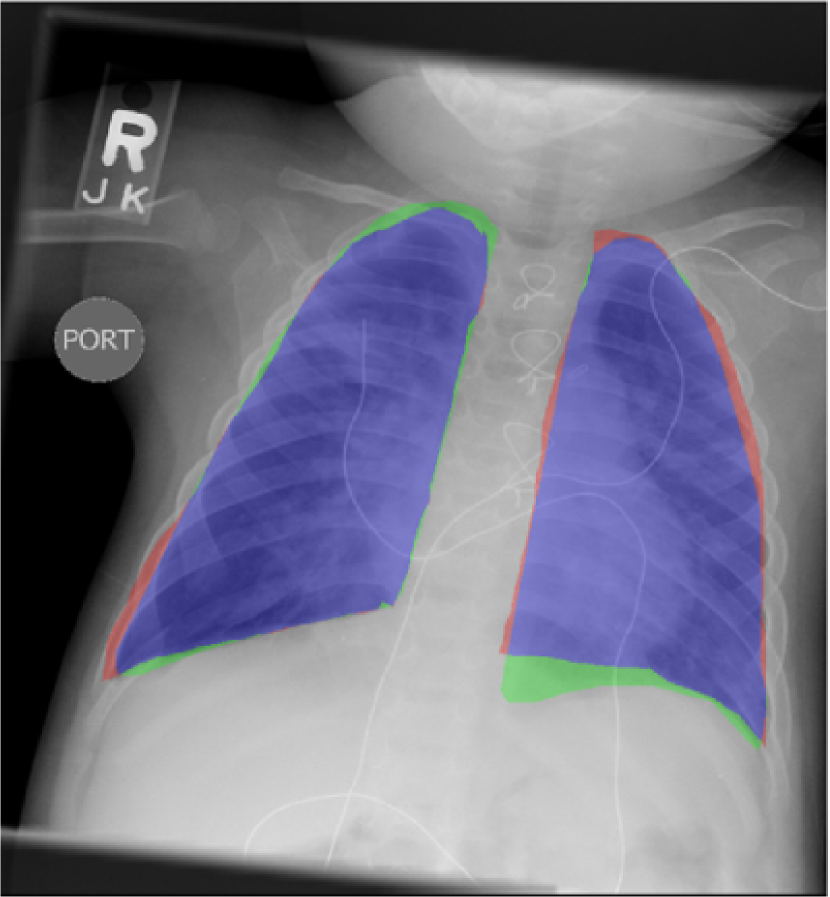

Fig. 9 presents the qualitative results of performing the lung segmentation using the proposed pipeline (ESL+MaShDL). The figure provides a visual insight on how inclusion of retro-cardiac region results in the segmentation label that is independent to the shape and structural changes in the close-by anatomical structures such as heart. For comparison purposes, similar qualitative results for the lung field labels obtained using the method proposed in [11] are provided in Fig. 10. As predicted before, the shape specificity is not preserved for the lung field labels obtained using [11]. This is further evident through the results presented in Table II. Moreover, unlike the proposed method, the U-net architecture uses an overlapping-based objective function (e.g., cross-entropy) which provides satisfactory results in cases with reduced shape variability. However, in the particular case of thoracic radiographs, the lung field labels without retro-cardiac space present higher shape variability than those observed when including this region. This could be a possible explanation of a slightly better overlapping-based performance (i.e., Overlap and DSC) by U-Net [11] when including the retro-cardiac space than without including it.